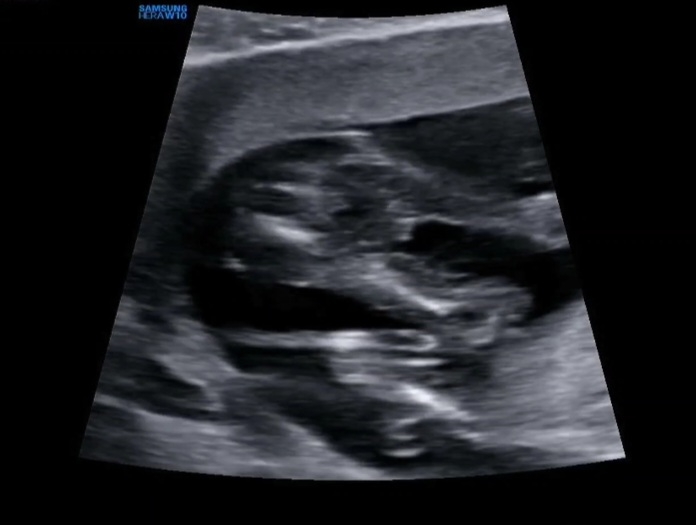

일란성 둥이들 14주 5일차 검진 때 초음파영상인데 성별은 아직 안 알려주셨거든요ㅠ 방광 괜찮은지 볼때 다리 사이가 찍혔는데 이 정도면 딸이라고 봐도 될까요?ㅎㅎ

딸인것같아요! 저는 15주에봤는데 아들은 뭐가 확실히 튀어나와있더라구여 ㅋㅋㅋ